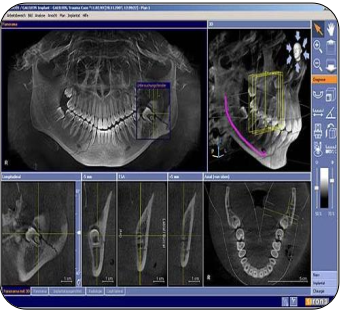

What is cone beam computer tomography? (CBCT)

Cone Beam Computed Tomography (CBCT):

• A 3D imaging technique using a cone-shaped X-ray beam and a digital detector that rotates around the patient.

• Produces detailed three-dimensional images of teeth, bone, and surrounding structures.

Used for:

• Implant planning

• Endodontic assessment (root morphology, resorption, fractures)

• Orthodontic evaluation

• TMJ and airway analysis

• Pathology detection

Advantages:

• Lower radiation dose than medical CT.

• High-resolution, accurate spatial representation.

• Allows precise measurements and cross-sectional views.